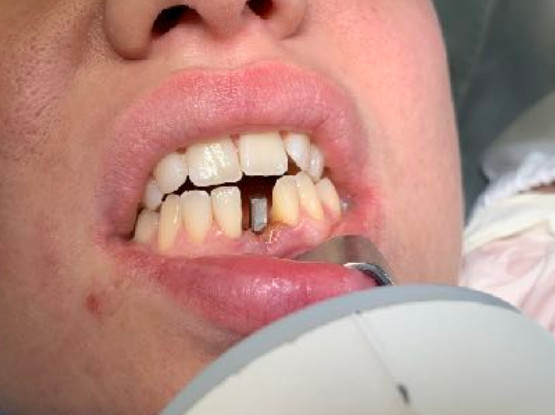

The reduced diameter of the neck allows you to protect yourself from any peri-implantitis and significantly improves the speed of healing. In this case it was tapped with a diameter of 4 and a Tramonte implant with a diameter of 4 mm with 7 threads with short neck was inserted. The titanium used is always grade 4.

| Extractive situation: Immediate post-extraction implant with immediate loading. | Density according to Misch: D2 |

| Occlusal loading: immediate light | |